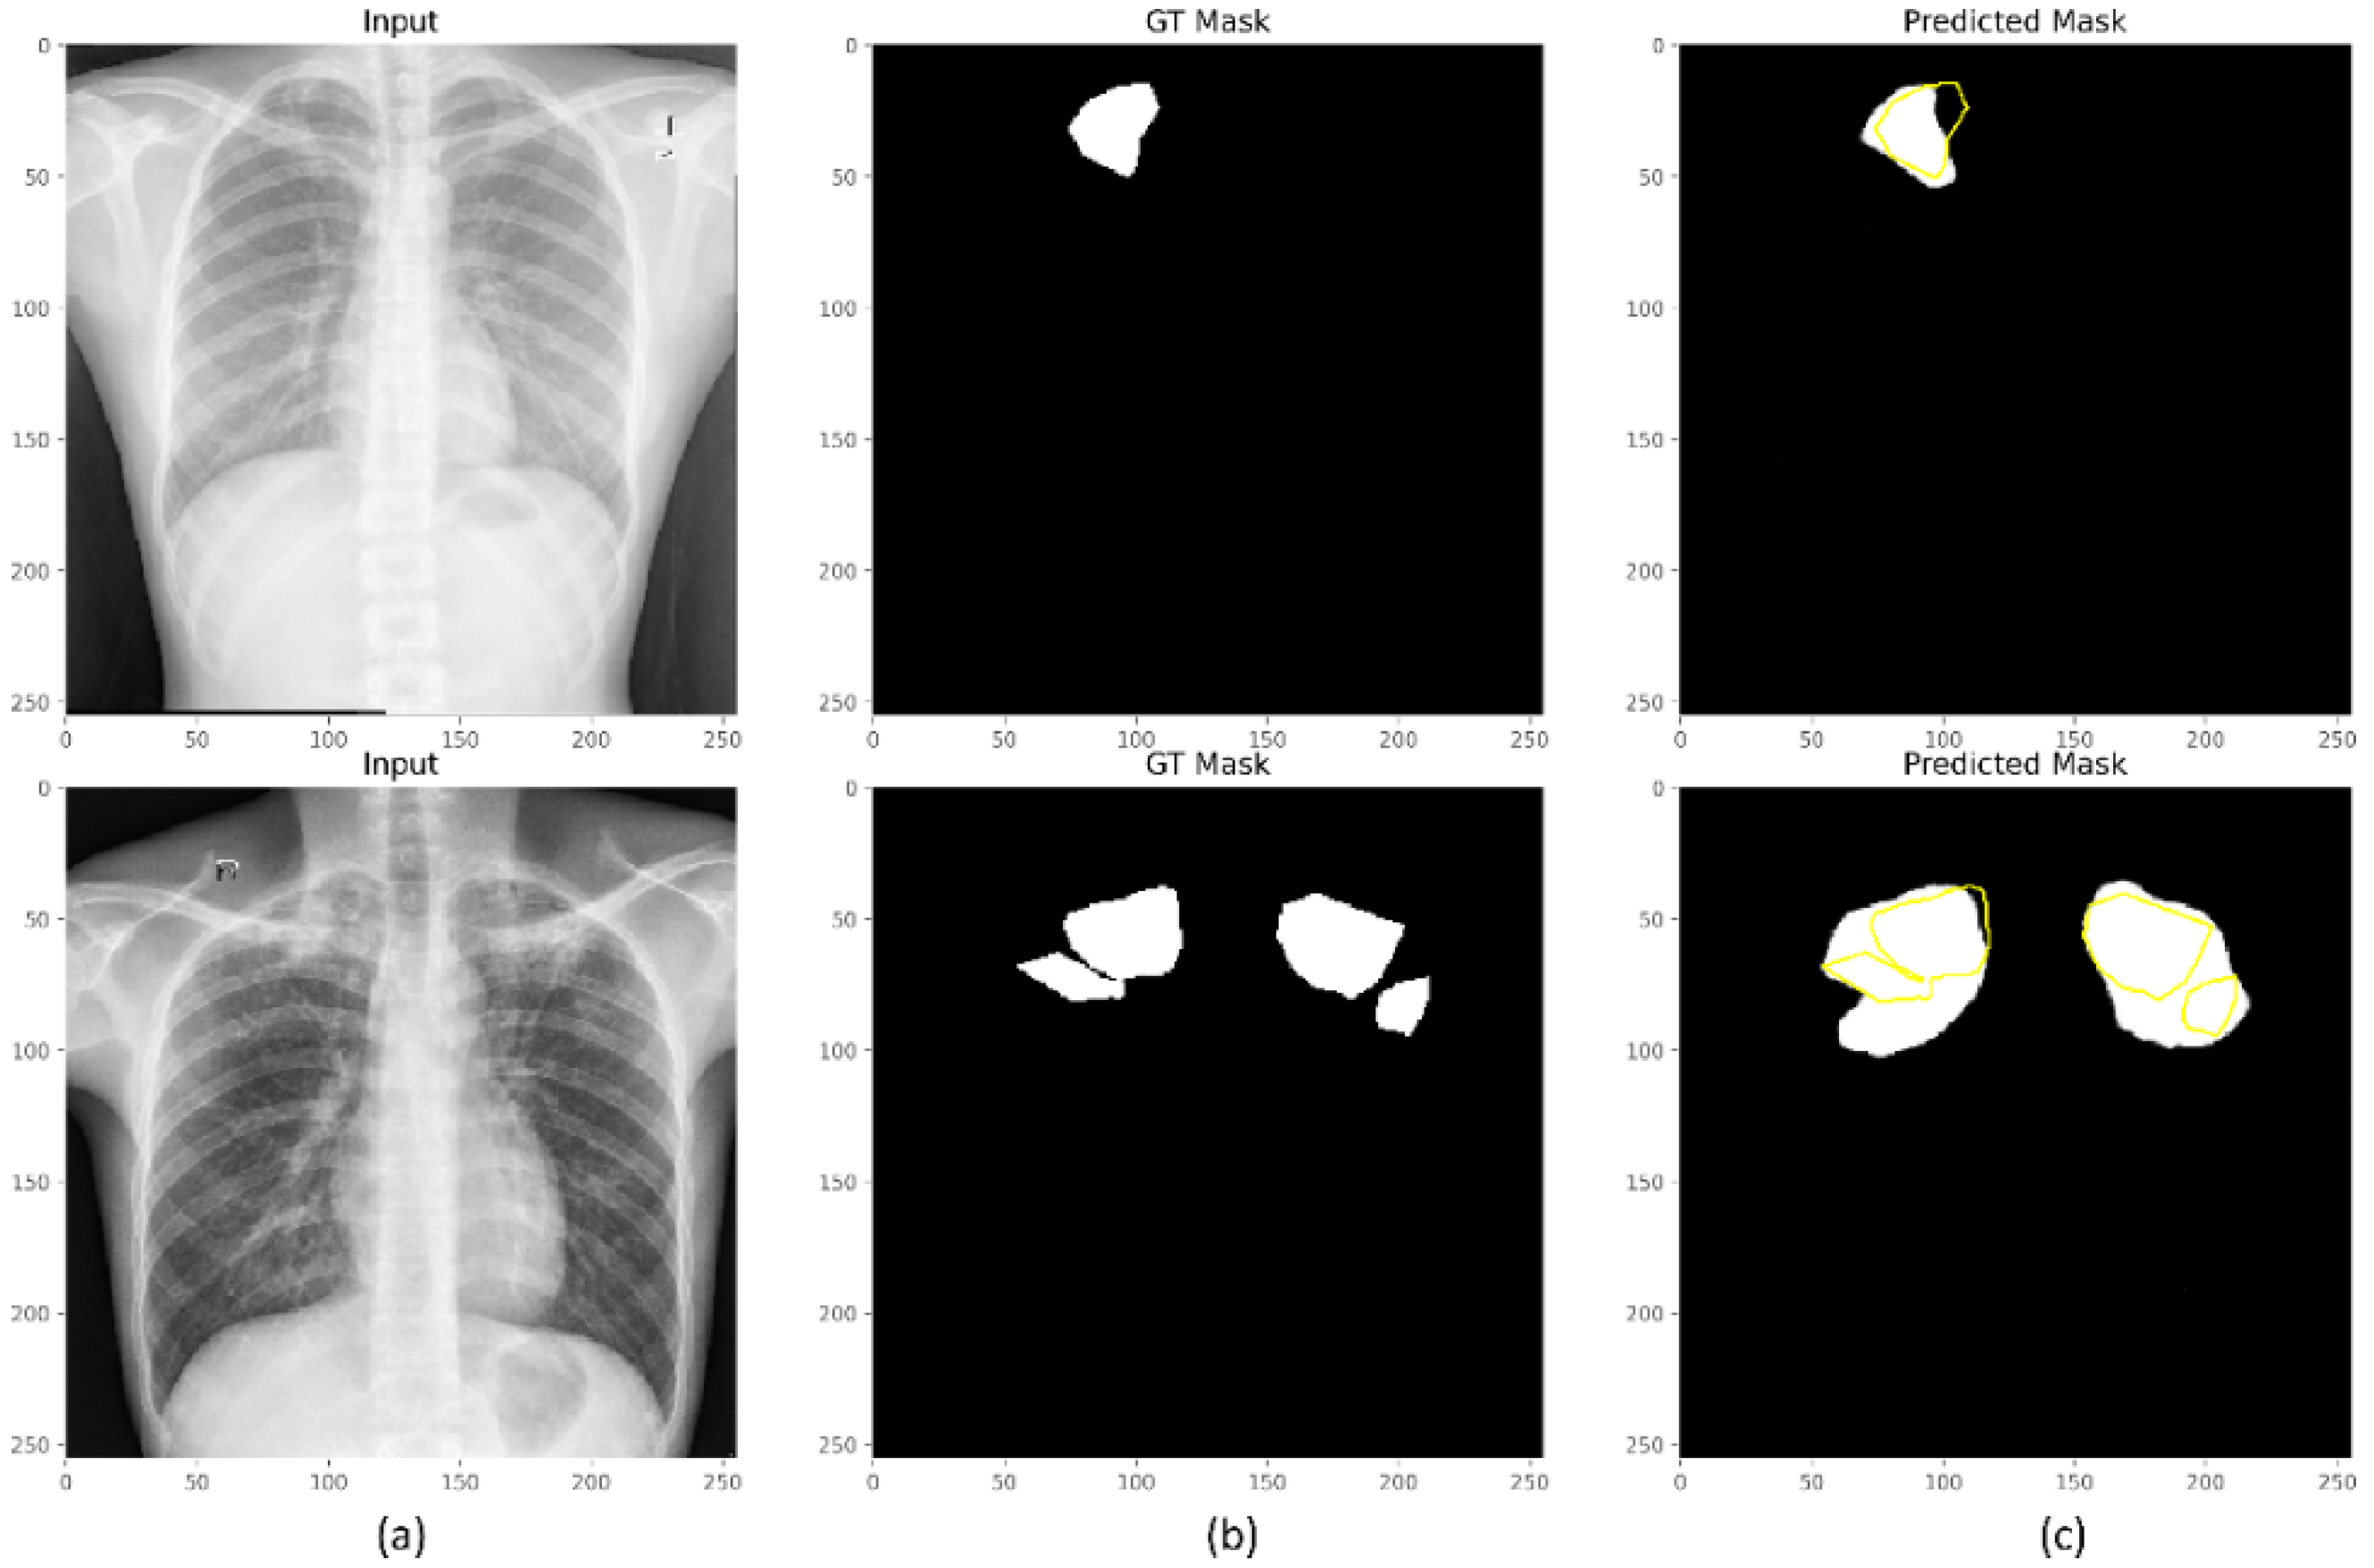

3.1. Segmentation Performance Achieved with the Proposed Loss Functions

3.2. Uncertainty Quantification